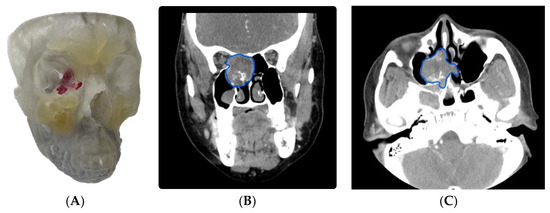

3.1.1. Case 1: Application of a 3D Model in Sinonasal and Skull Base Tumor Excision/Ablation